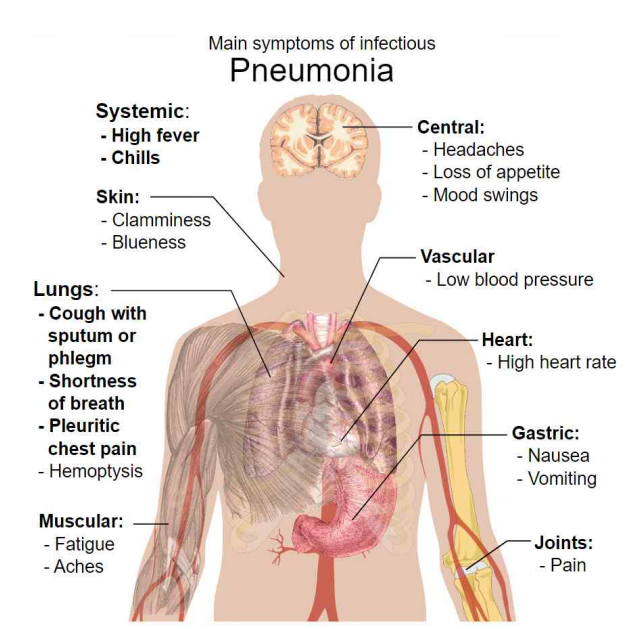

1. 감염성 폐렴 (Infectious pneumonia) 증상

흔한 증상으로는 기침(cough), 오한을 동반한 발열(fever accompanied by shaking chills), 숨가쁨(shortness of breath), 심호흡 시 날카롭거나 찌르는 듯한 흉통, 호흡 속도 증가 등이 있다. 노인의 경우는 혼란(confusion)이 가장 두드러진 징후일 수 있다.

발열(fever)은 다른 일반적인 많은 질병에서 발생하고 심각한 질병, 영양실조 또는 노인에게서 나타나지 않을 수 있으므로 특징적인 증상은 아니다.